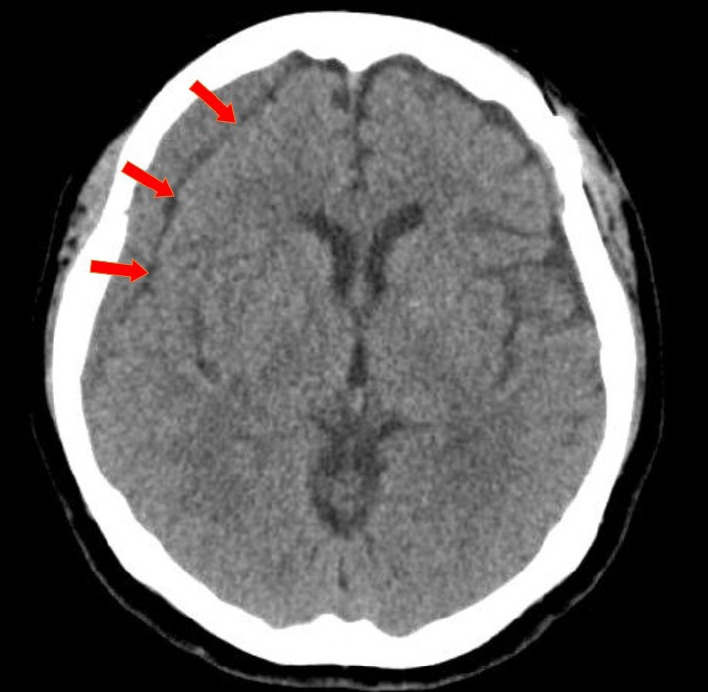

目的:慢性硬膜下血肿(CSDH)是剪切手术后的一种神经并发症。然而,与剪切相关的慢性硬膜下血肿(CSDH)的自然病程和理想治疗方法尚未明确。我们的目的是利用年代学影像学结果研究 CR-CSDH 的病程:我们对 2010 年 12 月至 2018 年 12 月期间在我院接受手术剪切的 736 例未破裂动脉瘤患者中的 28 例(3.8%)发生 CSDH 的患者进行了回顾性分析。患者在夹闭手术后6-8周接受随访CT扫描,并根据患者的症状(基于马克瓦尔德分级量表(MGS)和数字评分量表(NRS))决定是否进行手术干预:在28名患者中,3名患者(10.7%)接受了手术治疗,25名患者(89.2%)的CR-CSDH症状自行缓解。18名患者(64.2%)有轻微头痛,MGS为0-1。平均最大血肿量为 41.9±30.9 毫升(5.8-135 毫升),26 例患者(92.8%)的血肿为均质血肿。血肿消退的平均时间为(126.7±52.9)天(46-228 天)。比较CR-CSDH体积≥43毫升或中线移位≥5毫米的组别,发现保守组和手术组在是否存在线性低密度区(P=0.002)和年龄(P=0.026)方面差异有统计学意义:大多数CR-CSDH病例在4个月内自发缓解。因此,我们建议,尽管CR-CSDH体积相对较大且中线移位,但如果患者症状轻微且有特殊的影像学发现,则应密切观察。

Results: Of the 28 patients, 3 patients (10.7%) underwent surgery, while 25 (89.2%) showed spontaneous resolution of CR-CSDH. Eighteen patients (64.2%) had mild headache with MGS of 0-1. The mean maximum hematoma volume was 41.9±30.9 ml (5.8-135 ml), and 26 patients (92.8%) had homogeneous hematoma. The mean time to hematoma resolution was 126.7±52.9 days (46-228 days). Comparing group of CR-CSDH volume ≥43 ml or a midline shift ≥5 mm, the difference in presence of linear low-density area (p=0.002) and age (p=0.026) between the conservative and operative groups were found to be statistically significant.

Conclusions: Most CR-CSDH cases spontaneously resolved within 4 months. Therefore, we suggest that close observation should be performed if patient's symptoms are mild and special radiologic findings are present, despite its relatively large volume and midline shifting.